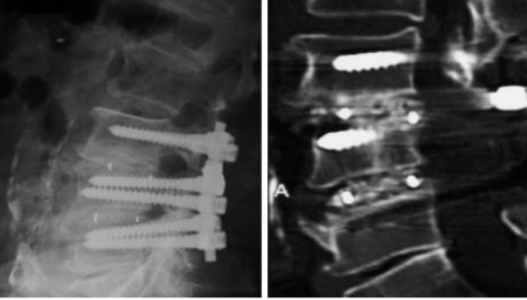

临床优势

1.良好的生物活性、结合植骨增强骨融合

2.椎间远期融合效果好,沉降率低